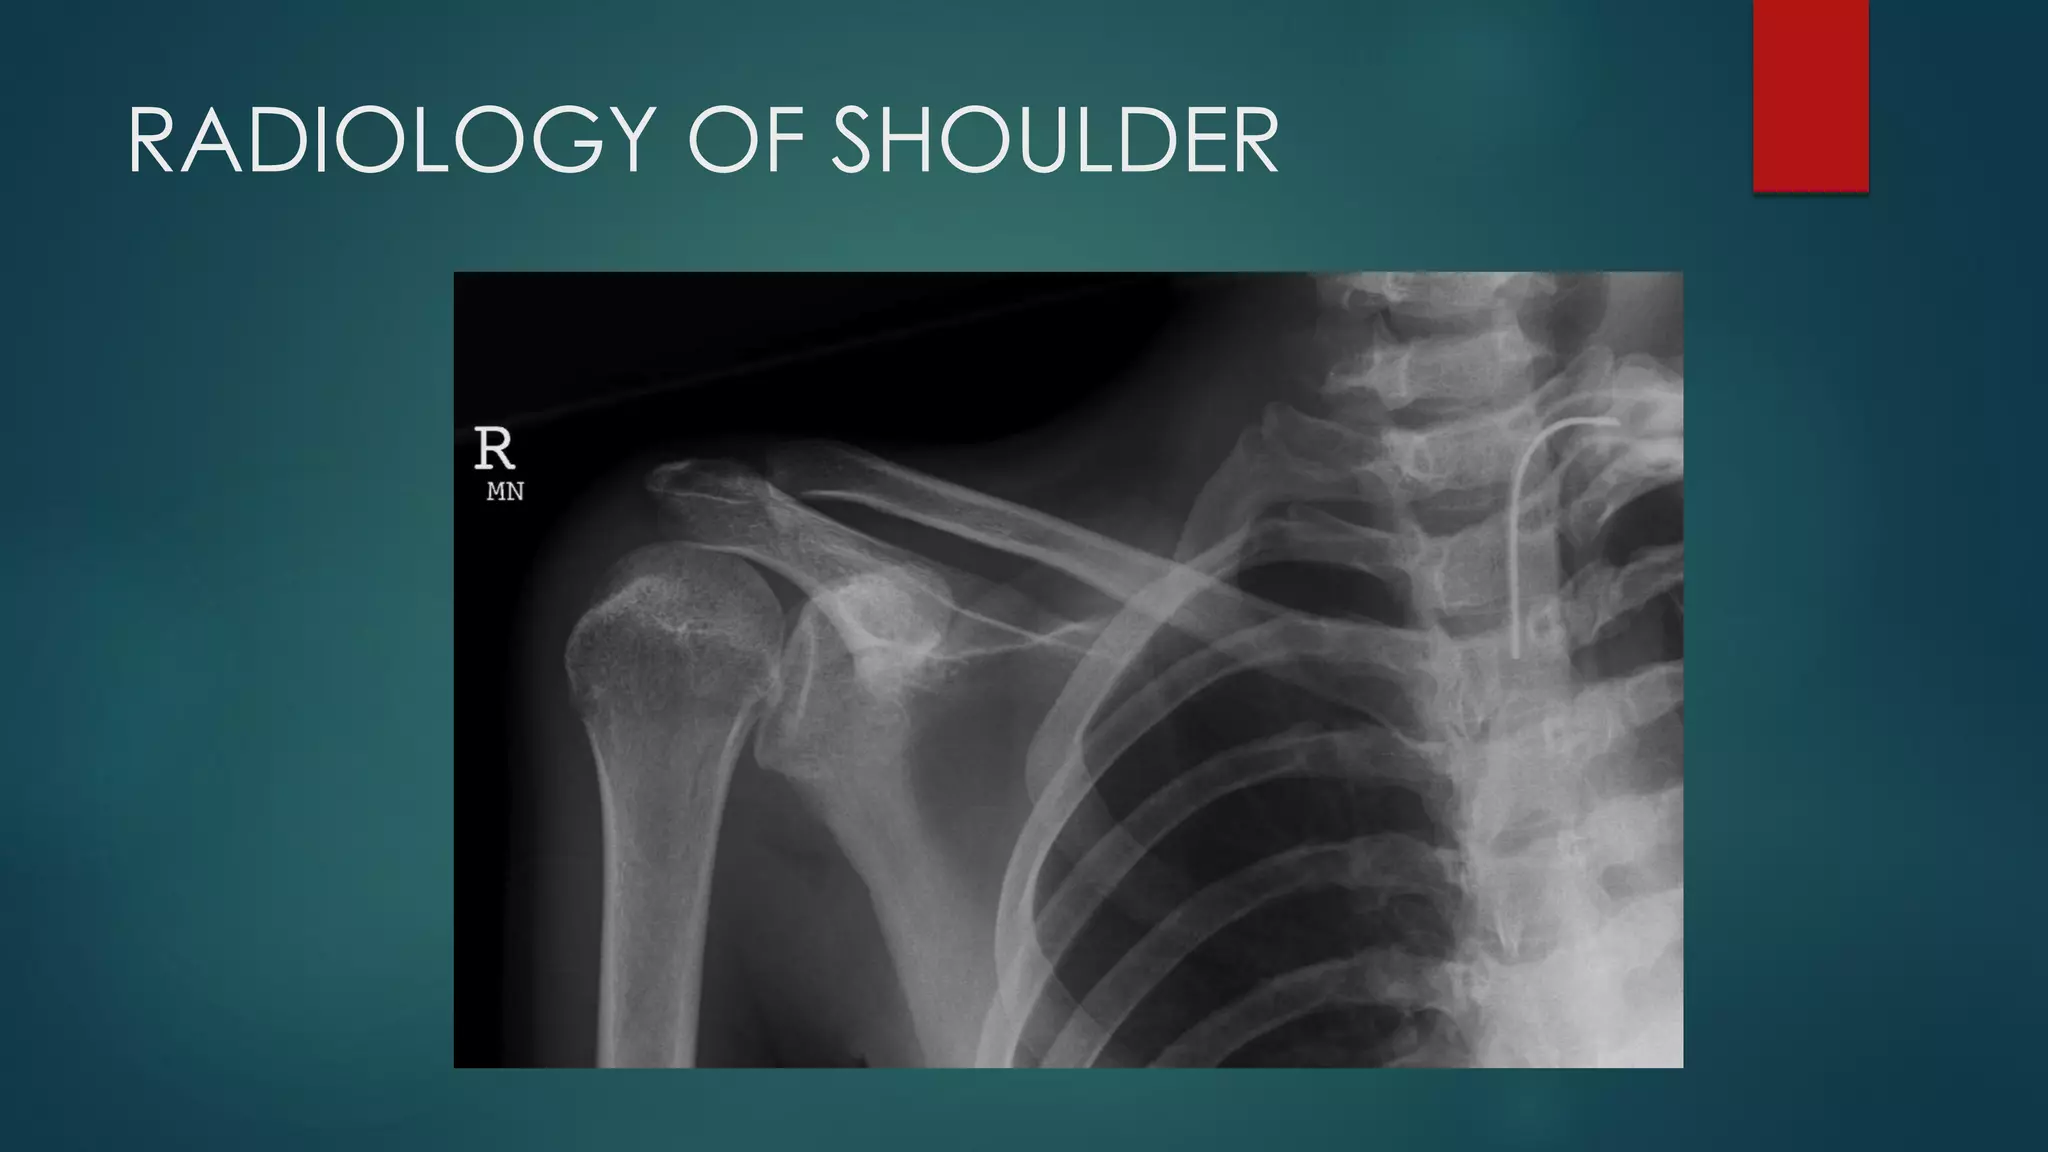

RADIOLOGY OF SHOULDER

ANTERIOR SHOULDER DISLOCATION SUBCAPITAL HUMERUS FRACTURE